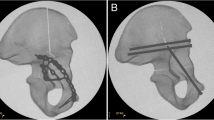

In both groups, the fracture was stabilized with a suprapectineal plate with quadrilateral buttress (PRO Pelvis and Acetabulum System, Stryker, Amsterdam, Netherlands) as the basic osteosynthesis. Bicortical 3.5 mm screws were used for fixation of the plate as it is shown in Fig. 1. For the APCS group, a 3.5 mm antegrade posterior column screw was inserted as described previously by Jung et al. outside the plate [21]. For the IAS group, a 3.5 mm infraacetabular screw was inserted as described previously by Baumann et al. through the fifth plate hole from ventral [40]. Both osteosynthesis constructs are illustrated in Fig. 1.

Fixation of a standardized generated anterior column plus posterior hemitransverse fracture with a suprapectineal plate plus an antegrade posterior column screw (A) or plus an infraacetabular screw (B). Red arrows indicate either the antegrade posterior column screw or the infraacetabular screw and the blue doted lines their respective course. The fracture lines are outlined in purple and the three main fracture lines are labeled

More precisely, it was demonstrated, that interfragmentary motion at the posterior hemitransverse fracture line (LX, shear XY) and at the high anterior column fracture line (LY) was significantly increased when an infraacetabular screw was used instead of an antegrade posterior column screw, each in combination with a suprapectineal plate. By contrast, fixation with an infraacetabular screw instead of an antegrade posterior column screw resulted in a reduced interfragmentary motion (LX, LY, LZ, shear XY) at the low anterior column fracture line. These results demonstrate that interfragmentary motion was increased at certain main fracture lines of the ACPHT fracture in both groups depending on the different screw courses. As it is illustrated in Fig. 5, the antegrade posterior column screw runs more perpendicular to the posterior hemitransverse fracture line and bridges the fracture line resulting in a higher fixation strength compared to the infraacetabular screw at this fracture line. In contrast, the infraacetabular screw runs more perpendicular to the low anterior column fracture line and bridges the fracture line resulting in a lower interfragmentary motion at this fracture line when an infraacetabular screw was used instead of an antegrade posterior column screw.